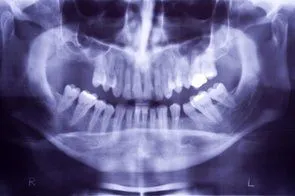

Loss of posterior teeth may result in excessive forces being placed on your remaining teeth. Fortunately, the use of dental implants and crowns allow you to replace these missing teeth. However, the position of the sinus in the upper posterior areas may be too low for proper placement of dental implants.

A simple procedure allows the sinus floor to be repositioned, creating enough space to properly place an implant. Various grafting materials are used to encourage your bone to grow more quickly into the area, helping to stabilize the dental implant. Replace with your own bone in this area the grafting material as it grows into the area.

Under certain conditions, an even simpler procedure can be utilized. When possible, the bone remaining under the sinus floor is gently “pushed up”, thus lifting the floor of the “dropped” sinus. Bone replacement materials are then placed beneath this lifted bone. Once again the bone materials are replaced as your body grow new bone into this area.

Sinus augmentation procedures are highly predictable, with studies reporting over 95% success. Following sufficient healing of a sinus augmentation (6-10 months), implants are placed in a predictable and successful manner. It is important to realize that if the sinus augmentation procedure does not result in enough bone for implant placement, additional bone may be regenerated through a second sinus augmentation procedure at the time of implant placement.